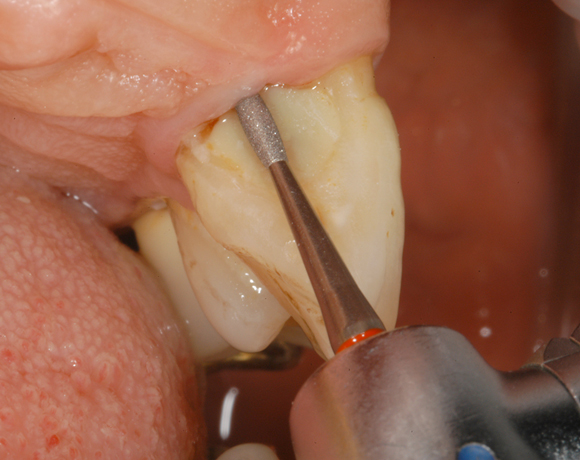

(Diamant- und Hartmetall-Instrumente Periodont Set) Zwei unterschiedliche Formen in zwei unterschiedlichen Schaftlängen, jeweils in Hartmetall und Diamant, erlauben die individuelle Behandlung der Wurzeloberfläche.

Das Periodont Set im Einsatz.